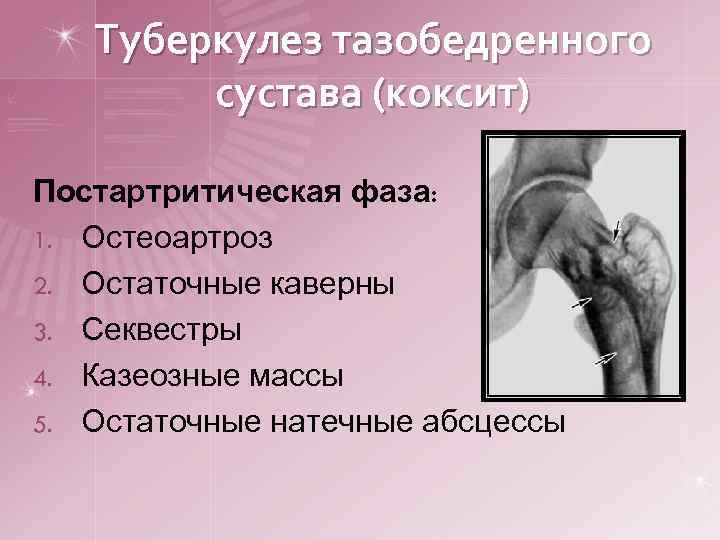

Туберкулез тазобедренного сустава (коксит) Постартритическая фаза: 1. Остеоартроз 2. Остаточные каверны 3. Секвестры 4. Казеозные массы 5. Остаточные натечные абсцессы